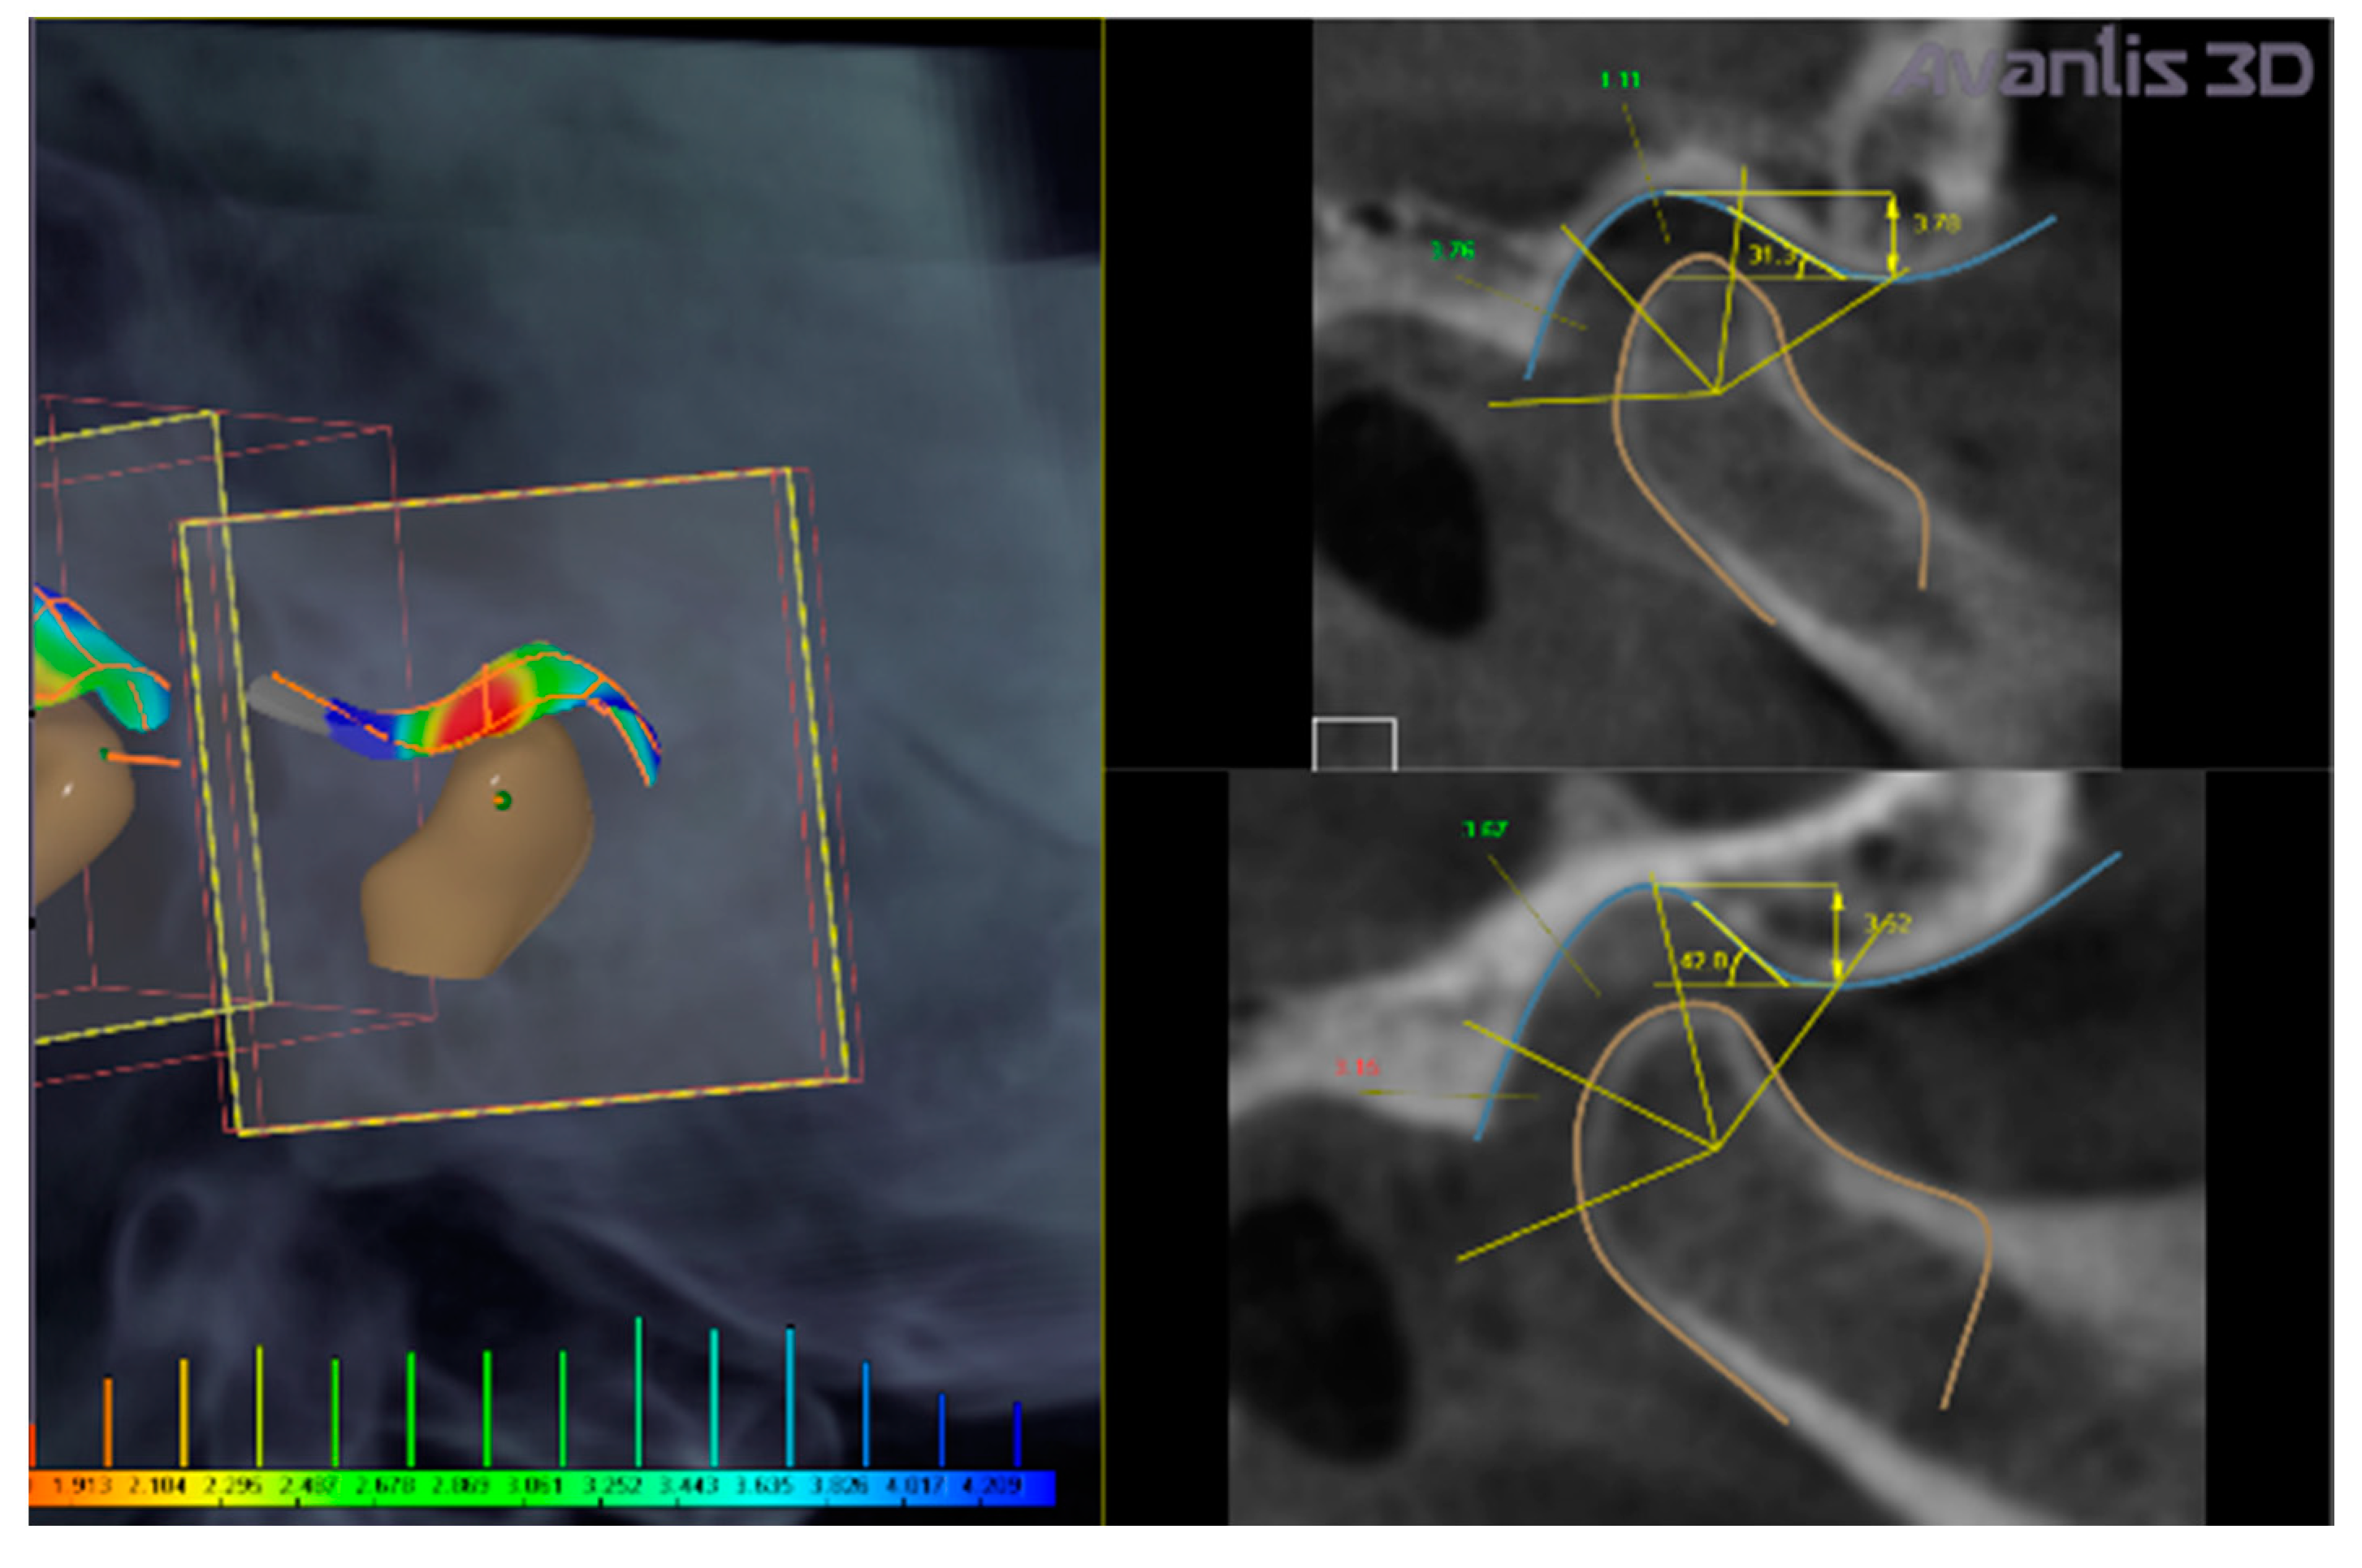

• Calculation of intra-articular spaces width (in mm) (anterior, superior, and posterior spaces) executed by the software (Figure 4).

In the present clinical case, CBCT images revealed a narrowing of the posterior intra-articular space width, in respect to normal values established by Rabukhina, that are: 1.7–2.7 mm for the anterior width; 3.1–3.9 mm for the superior height; and 3.4–4 mm for the posterior part) (Figure 3 and Figure 4) [21,22,23].

The left condyle was repositioned by: −0.4 mm in the transversal plane, 0.8 mm in the sagittal plane, and 0.9 mm in the vertical direction. The right condyle was repositioned by 0.4 mm, 1.2 mm, and 1.3 mm, respectively, in the three planes (Figure 4).

The virtual rotation was established at 0.4 degrees (Figure 4) to obtain the normalization of superior and posterior space widths.

In the present case, a full digital workflow was adopted for the patient. Mandibular repositioning was established automatically by the software, which moved the mandible to normalize the intra-articular space widths (Figure 4).

The software was set on the following values of intra-articular space width: for the anterior space in the range of 1.7–2.7 mm, for the superior space in the range of 3.1–3.9 mm, and for the posterior space in the range of 3.4–4.0 mm. Then, the software calculates the intra-articular widths of the clinical case. The intra-articular widths are determined with the software as follows: the most prominent points on the right and left sides of each condyle are individuated on the contours of the horizontal sections of each condyle; then, the most distant points are determined on these contours. Then, segments connect these points, for each condyle, to the glenoid fossa. A total of 45 cross-sections are built along these segments for each condyle. On each section, the distances between condyle and fossa for distal, upper, and medial part are measured (the range of measurements in the present clinical case are reported in Figure 4 and Figure 9). The final value is determined as mean and standard deviation of the whole sample of measurements.

Figure 3. Calculation of intra-articular space widths on CBCT taken in habitual position. Colors evidence reduced (red), normal (green), and increased (blue) intra-articular space widths ranging from 1.9 to 4.2 mm.